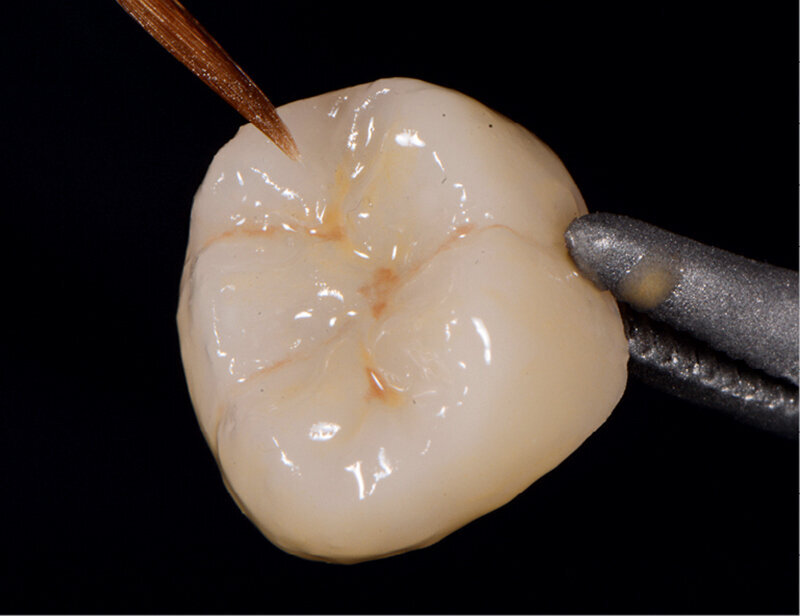

Fig. 4: Characterised and glazed crown.

A 45-year-old male patient presented to the practice with a restoration on tooth #46. The tooth had been endodontically treated and temporised with a filling (Fig. 1). The temporary was removed, the tooth built up with Tetric N-Ceram Bulk Fill (Ivoclar Vivadent) and then prepared for the crown restoration (Fig. 2). An impression was taken with a one- step, two-phase impression technique using a putty and light-body silicone. After scanning the model, the crown was designed in the software suite (inLab, Dentsply Sirona) and milled from an IPS e.max CAD lithium disilicate block (Ivoclar Vivadent; Figs.3a & b). After the crystallisation fir- ing, the crown was stained and glazed (Fig. 4). The next step was to etch and silanate the ceramic crown with the new glass-ceramic primer Monobond Etch & Prime (Ivoclar Vivadent). This primer combines a ceramic etching and silanating component in a single material and therefore eliminates the need for the ceramic to undergo hydrofluoric acid etching (Fig. 5). After the etching and silanating step, the crown was rinsed with water and dried. The isolated enamel was then etched (Fig. 6). The adhesive (Tetric N-Bond Universal) was applied and dispersed with a strong stream of air. The dual-curing version of the Variolink Esthetic luting composite was used for seating owing to the thickness of the crown and the low translucency of the ceramic material (Fig. 7). The luting composite was applied into the crown. The restoration was then seated (Fig. 8) and light-cured from each side for two seconds. Excess composite was easy to remove owing to the Ivocerin photoinitiator (Ivoclar Vivadent), which provides a fast and thorough cure with a minimum amount of energy (Fig. 9). For final polymerisation, the restoration was light-cured from each quarter for 20 seconds (Fig. 10). Figures 11 and 12a & b show the oral situation after placement of the crown. Although the cement line was located above the gingival margin, it was not visible owing to the favourable tone and opacity of the luting composite. Figures 13a & b show radiographic control images of the restoration: the radiopaque build-up material and cement can easily be distinguished from the tooth structure. This aspect is particularly important in situations where excess cement cannot be seen with the naked eye.